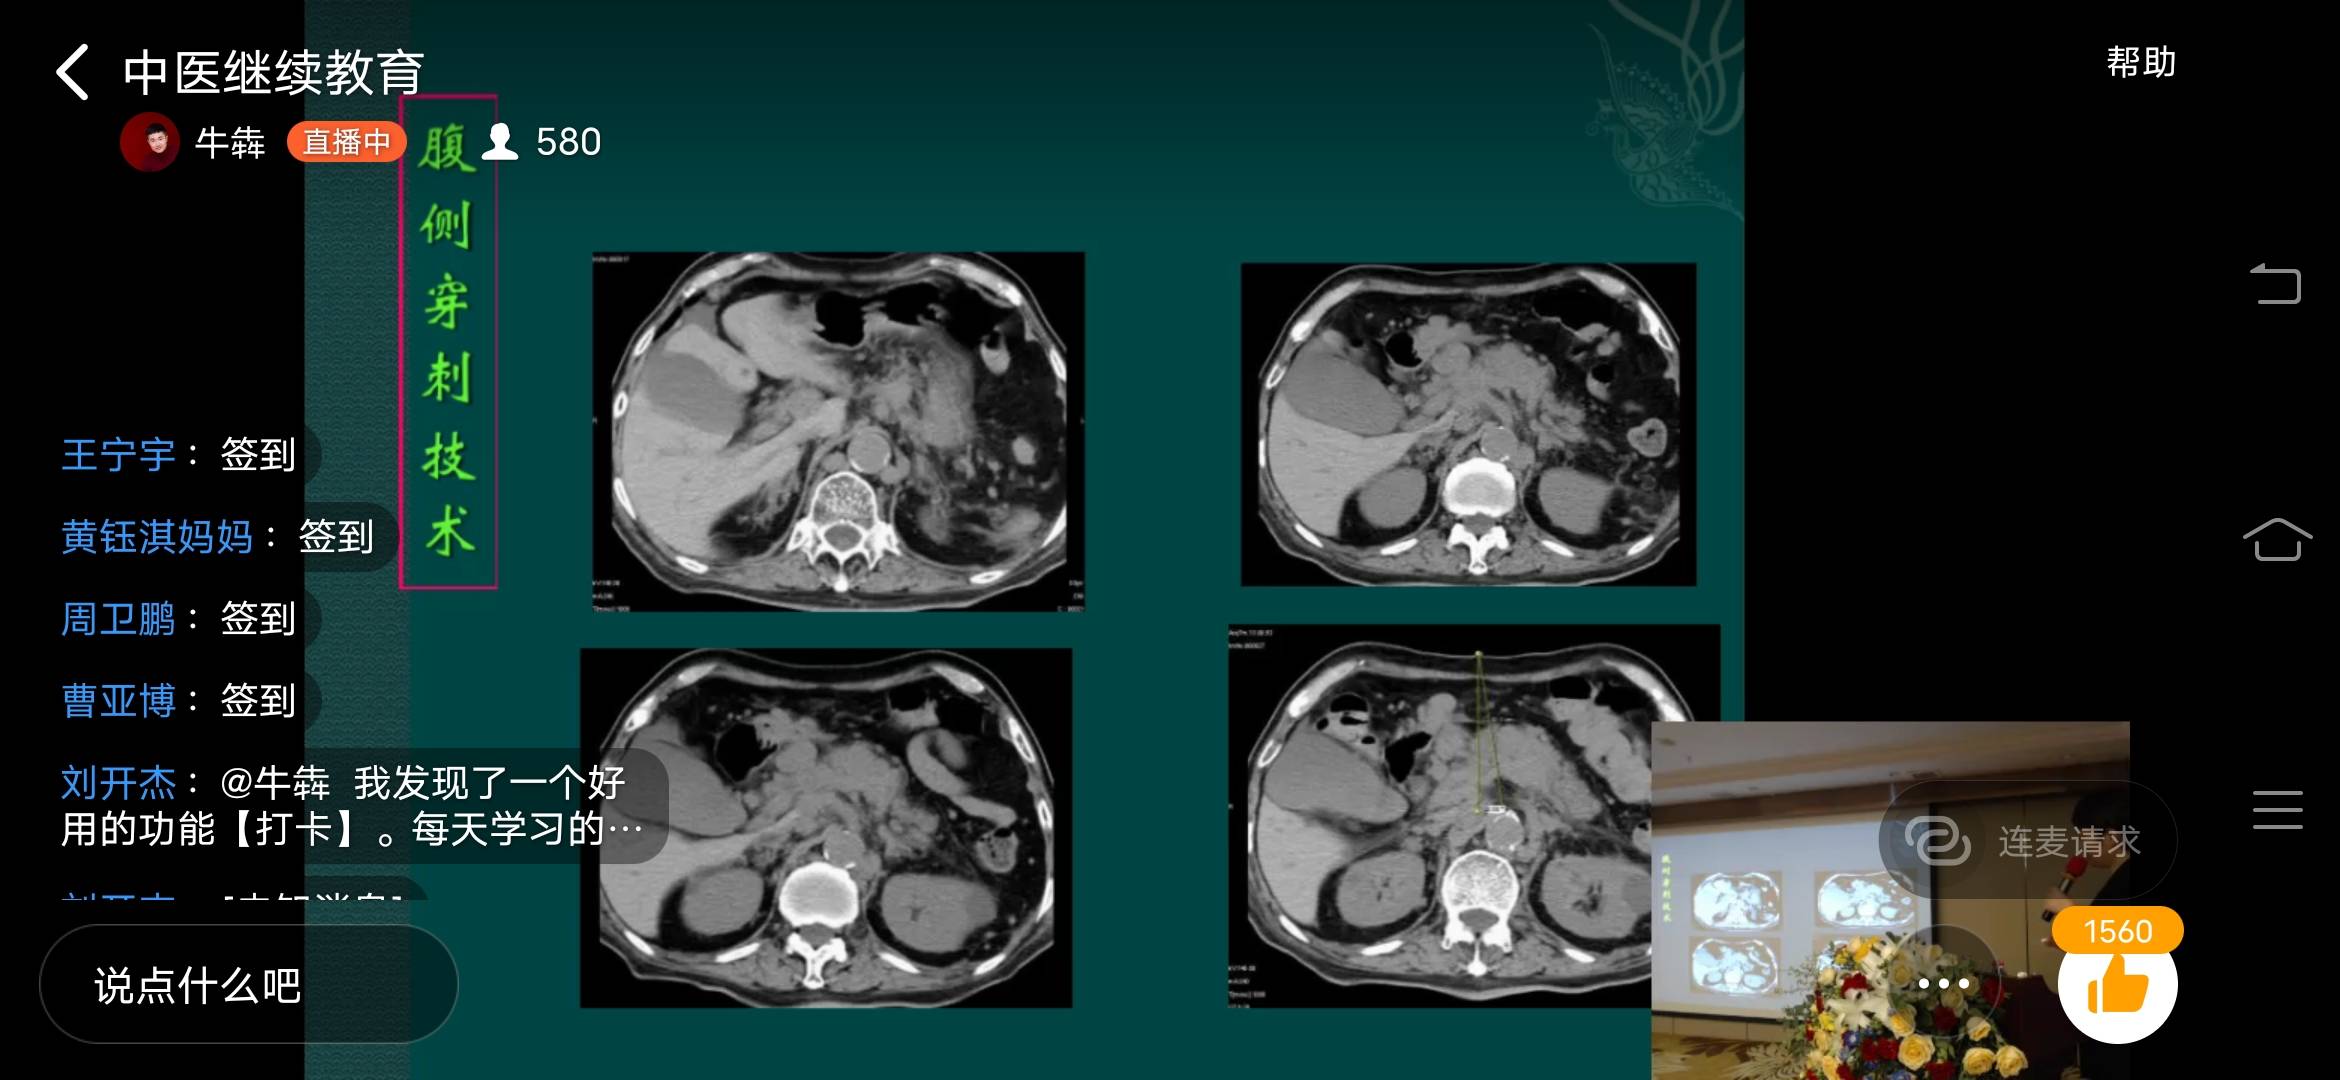

新闻速递|我院顺利举办2020年郑州市中医继续教育项目

2020年9月26日,由郑州济华骨科医院主办的2020年郑州市中医继续教育项目《影像引导下的微创介入治疗》,在郑州市维也纳酒店会议厅顺利召开. 会议邀...